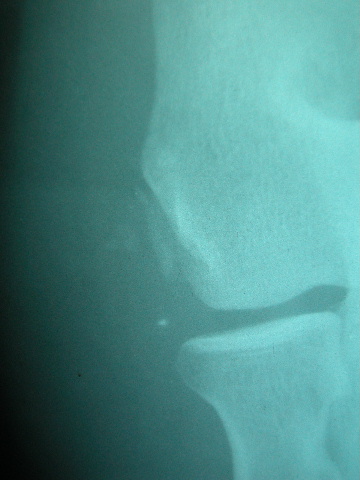

APR Arrancamiento de epífisis distal